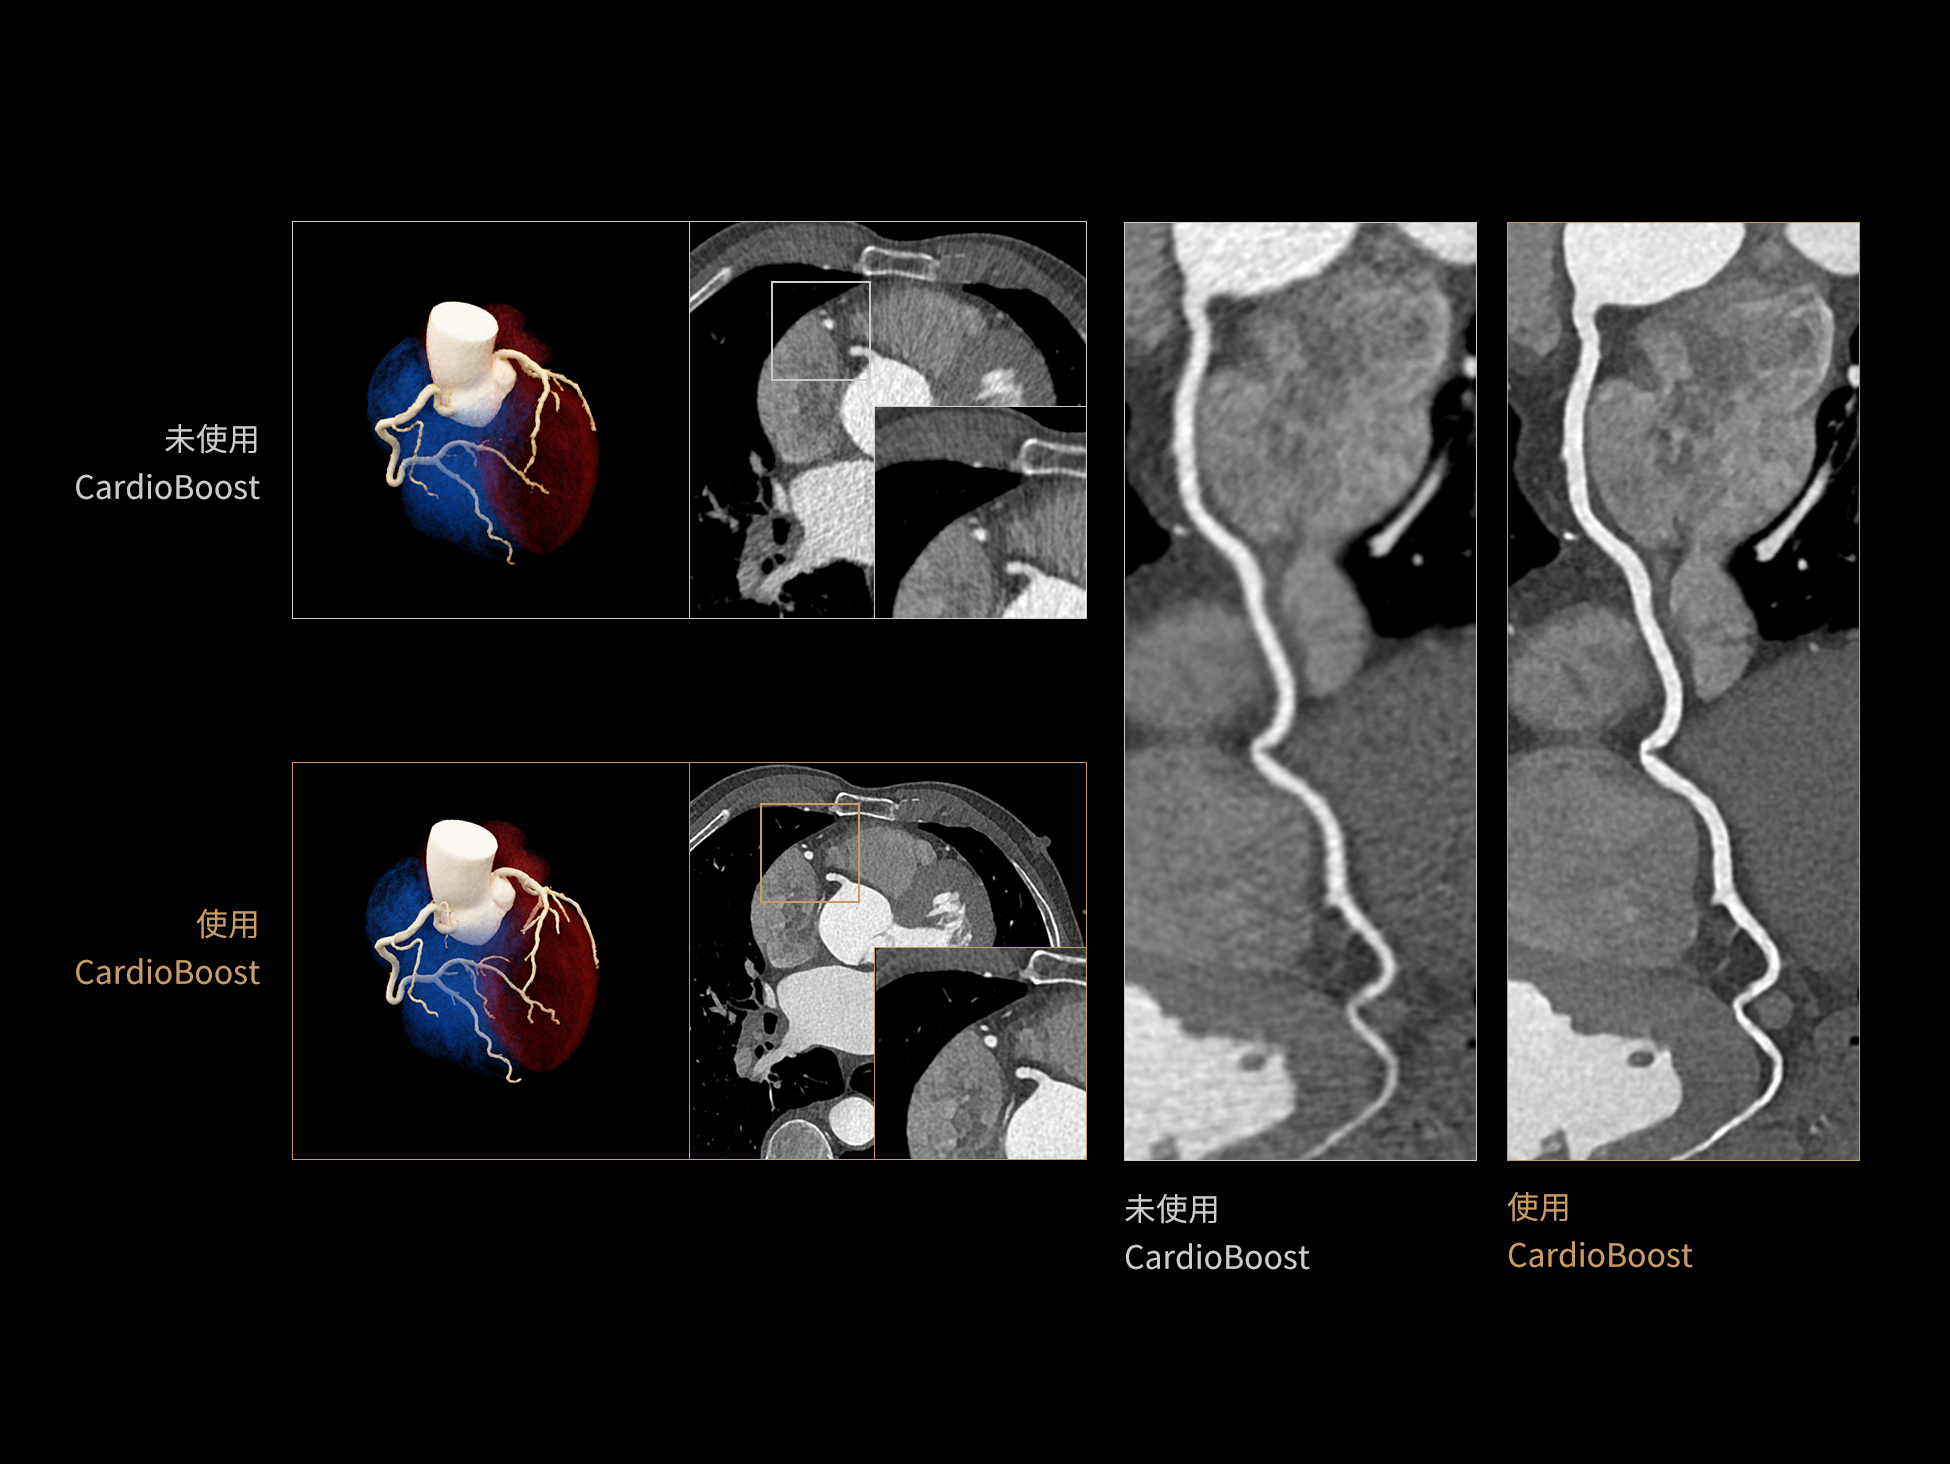

CardioBoost:专属网络设计,重塑心脏影像表现

uCT 868 搭载联影最新一代 uSense 人工智能平台,将智能化深度融入 CT 扫描全流程,从感知细微生理运动到精细结构探测,再到多场景诊疗优化。以 AI 为核心驱动力,uSense 重塑成像各环节,打造高效、高清的智慧扫查体验。在心脏成像领域,uSense 结合宽体探测器、心脏专研AI重建算法与AI冠脉运动追焦技术,在保持低剂量的同时,有效抑制运动伪影,精准呈现软斑块、混合型斑块及支架细节,助力冠脉成像惠及更多患者。针对多科室疾病临床应用场景,uSense 平台提供全方位的智能解决方案:包括头部运动伪影智能校正、金属植入物伪影抑制、扫描视野扩展等先进算法。这些创新技术使 uCT 868 能够构建覆盖全场景的智能诊疗体系,持续拓展 AI 赋能医学影像的边界。